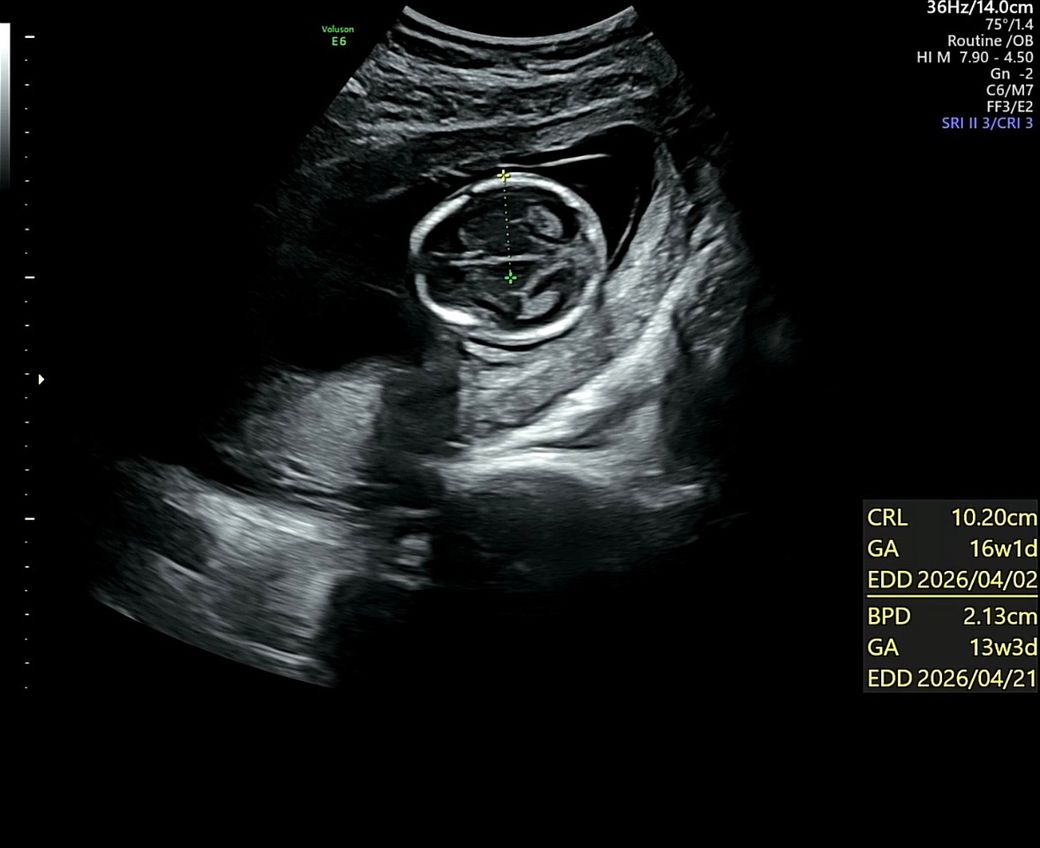

16주에 2차 기형아 검사 결과로 신경관결손 얘기를 들았고 수치는 6.4….나왔습니다.양수검사 받아보라고 병원에서 얘기했으나 양수검사는 받지 않기로 마음먹고 서울 대학병원 정밀초음파 예약 잡아놓은상태입니다..아직 예약일까지 3주 가까이 남아서 숨이 턱턱 막히고 하루하루가 불안하지만 아기를 믿고 운명을 믿는수밖에 아무것고 할수 있는게 없네요.. 기존 산부인과 선생님도 초음파 다시 돌려보면서 혹시 본인이 놓친것이 있나 다시 봤는데 문제는 없어보였으나 아직 아기가 너무 작아서 안보일수도 있다고 하더라고요.. 대학병원 예약일에는 19주 5일 예정입니다..온라인상으로는 질문 안하고 싶었으나 하루하루가 너무 초조해서 글남겨 봅니다전문의 분들 보시기에 아기 머리 모양에 의견을 구할 수 있을까요?

• 2번 째 사진